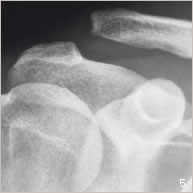

Lors d’un traumatisme au niveau de l’épaule, ces ligaments peuvent être rompus. L’articulation acromio- claviculaire n’est plus maintenue, l’épaule et l’omoplate sont tirées vers le bas par la pesanteur et la clavicule est ascensionnée par les muscles (figures 2 et 5). On parle alors de luxation acromio-claviculaire responsable de douleur et de déformation visible.